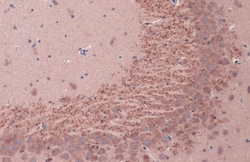

Keep as concentrated solution. Predicted reactivity: Mouse (100%), Rat (100%), Dog (100%), Cat (100%), Pig (100%), Chimpanzee (100%), Bovine (100%). Positive Control: mouse brain, rat brain, BDNF-transfected 293T. Store product as a concentrated solution. Centrifuge briefly prior to opening the vial.

| Immunohistochemistry (Frozen), Immunohistochemistry (Paraffin), Western Blot, Immunocytochemistry | |

| Human, Mouse, Rat | |